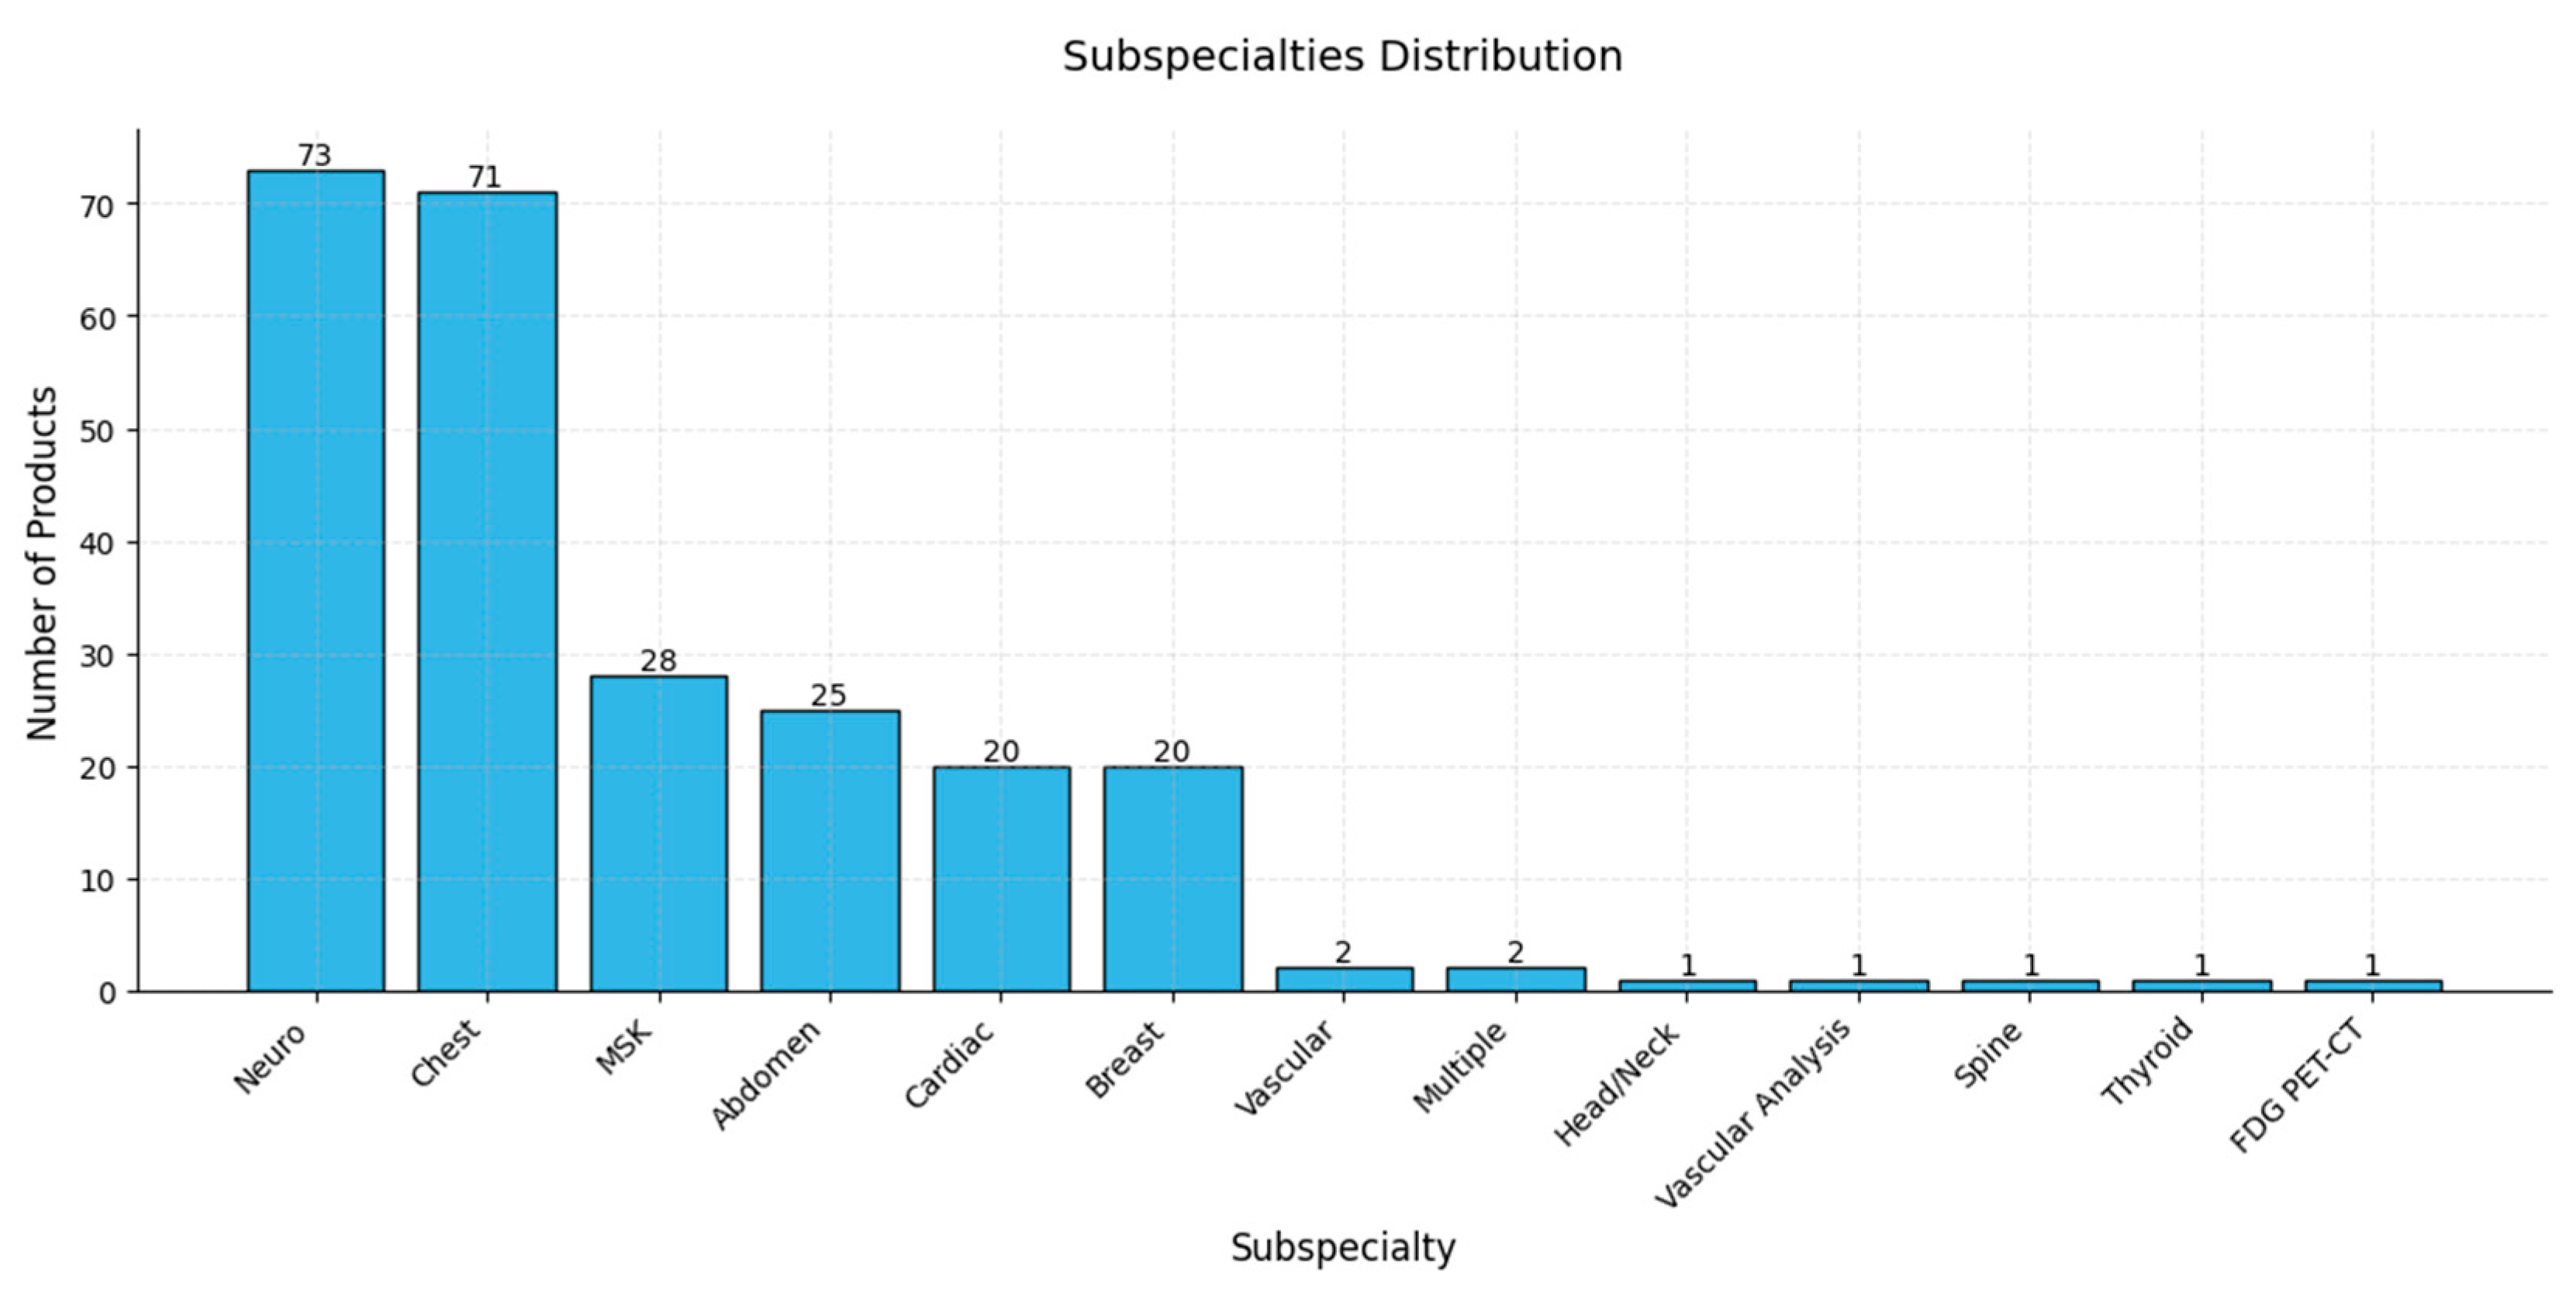

9. Review of AI Products Used in Radiology: Status in 2024